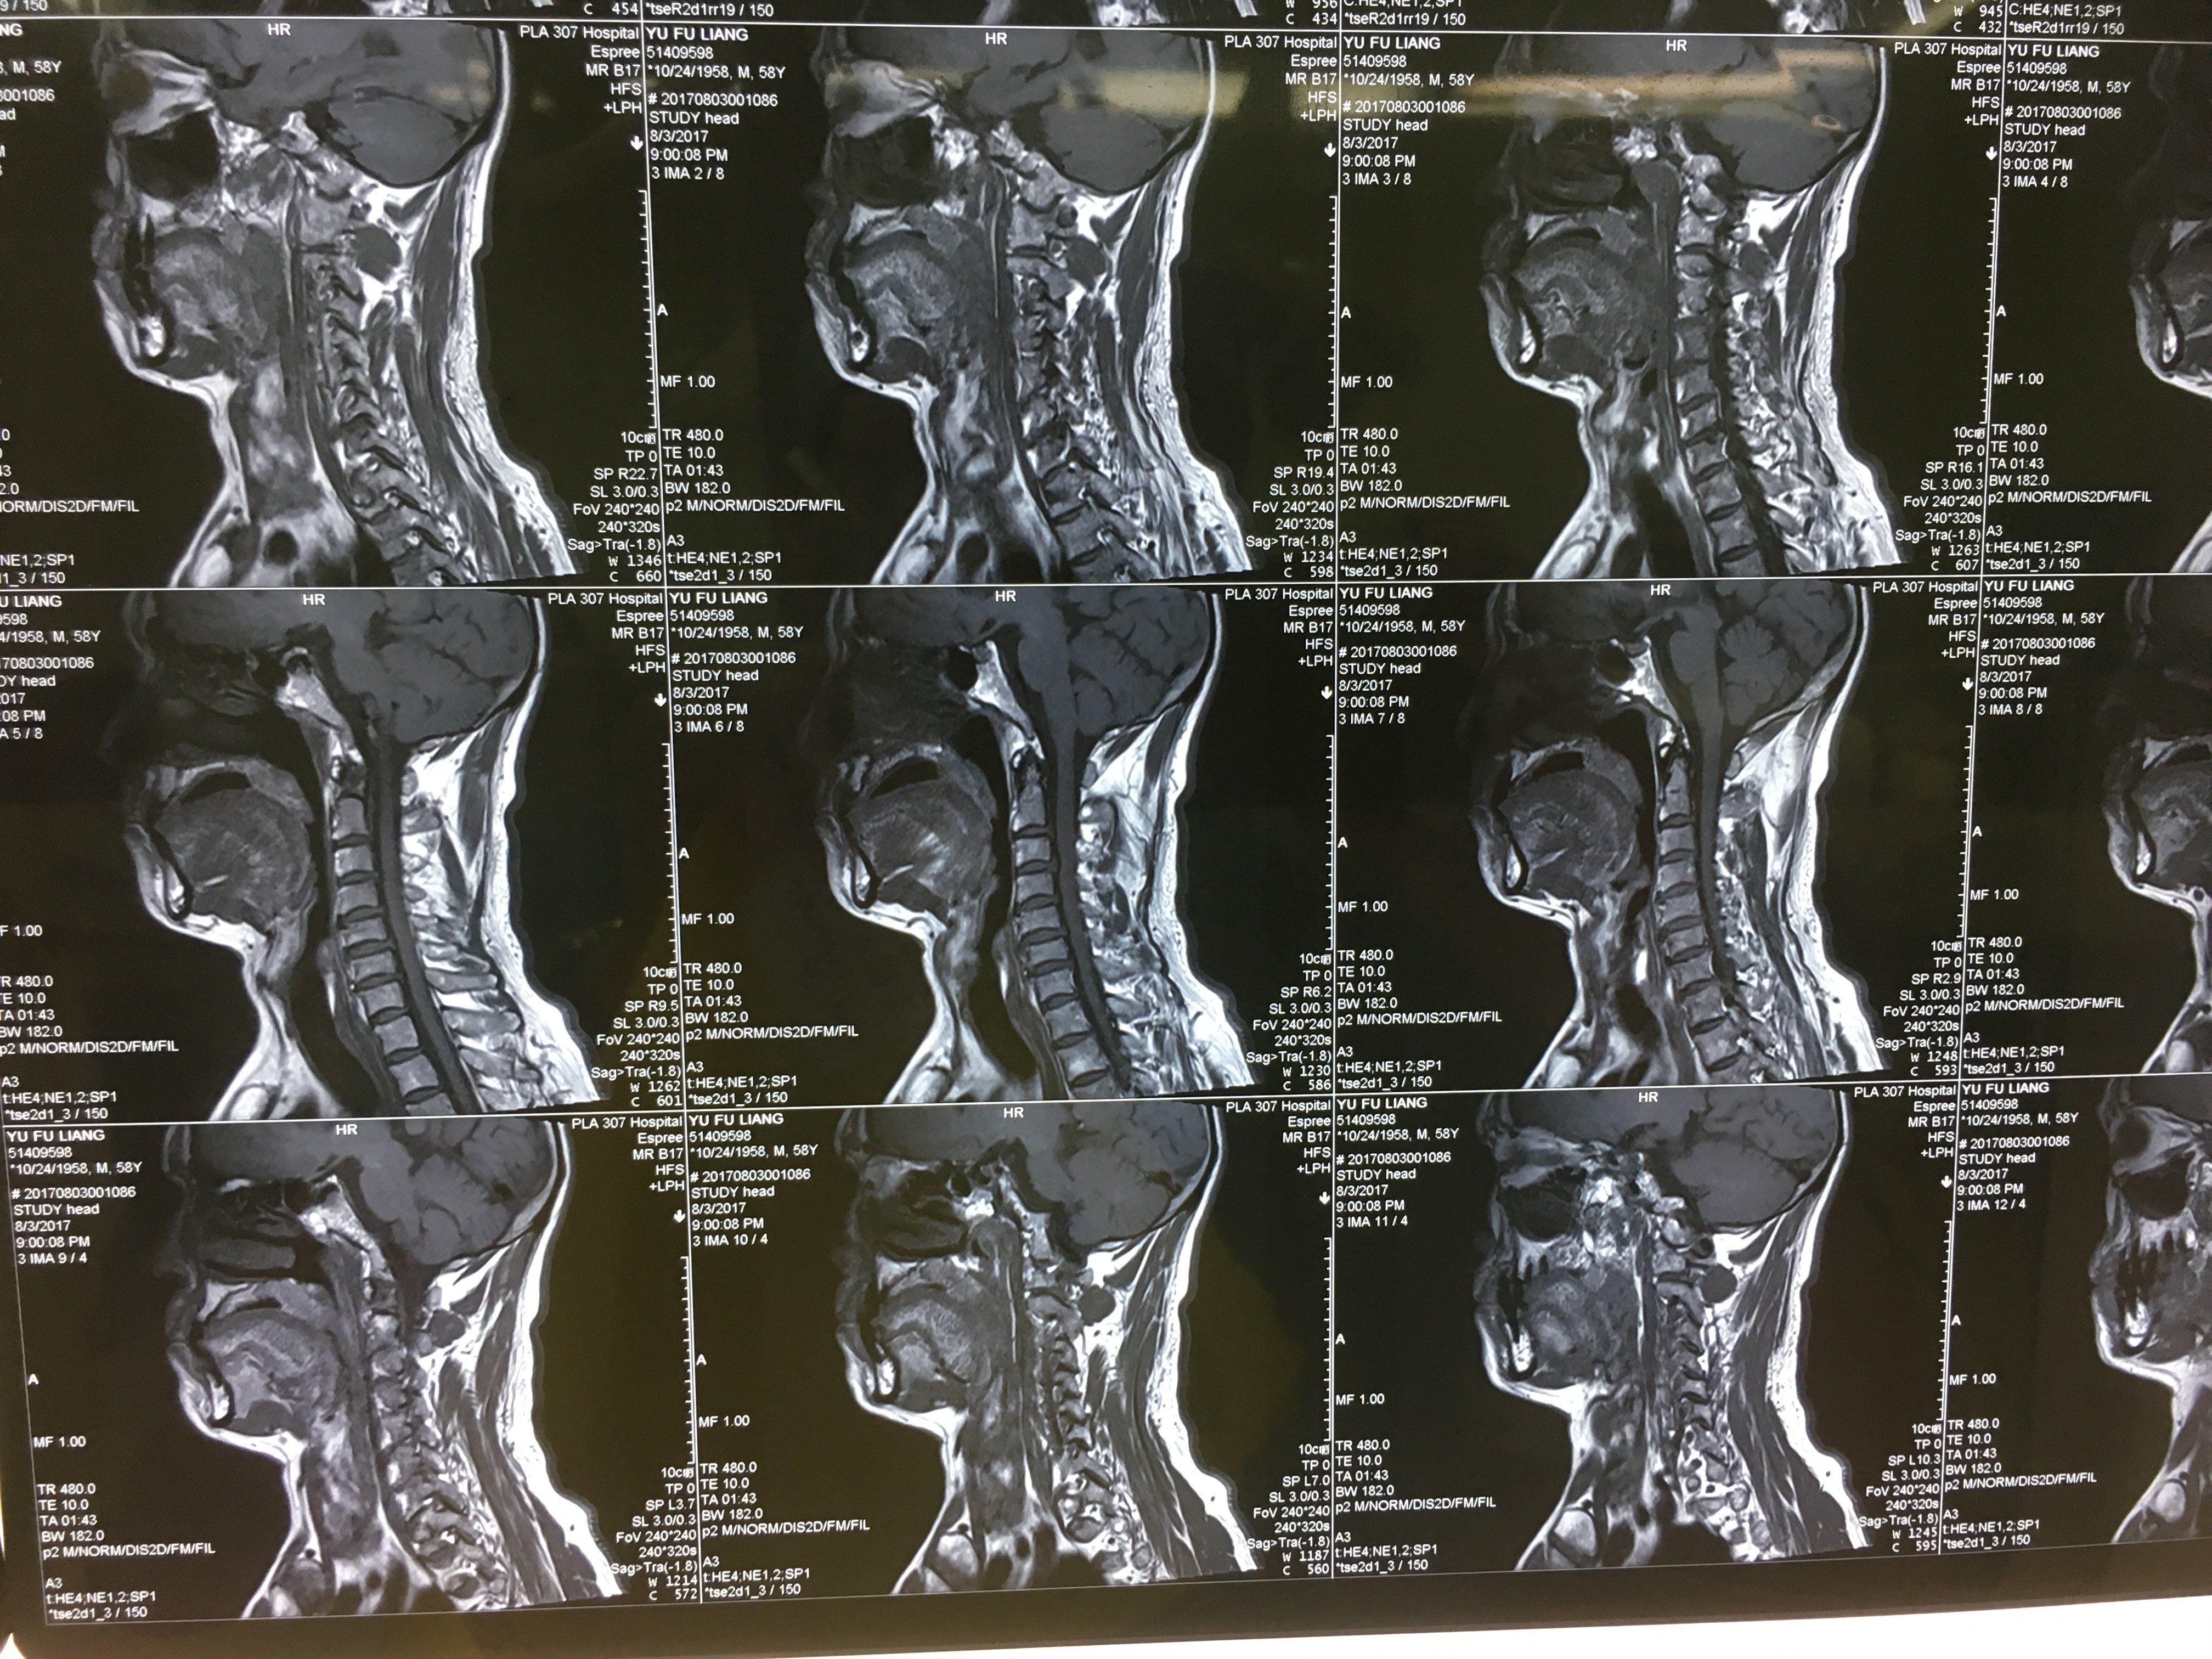

病例 Acdf手术治愈颈椎间盘突出一例 网易订阅